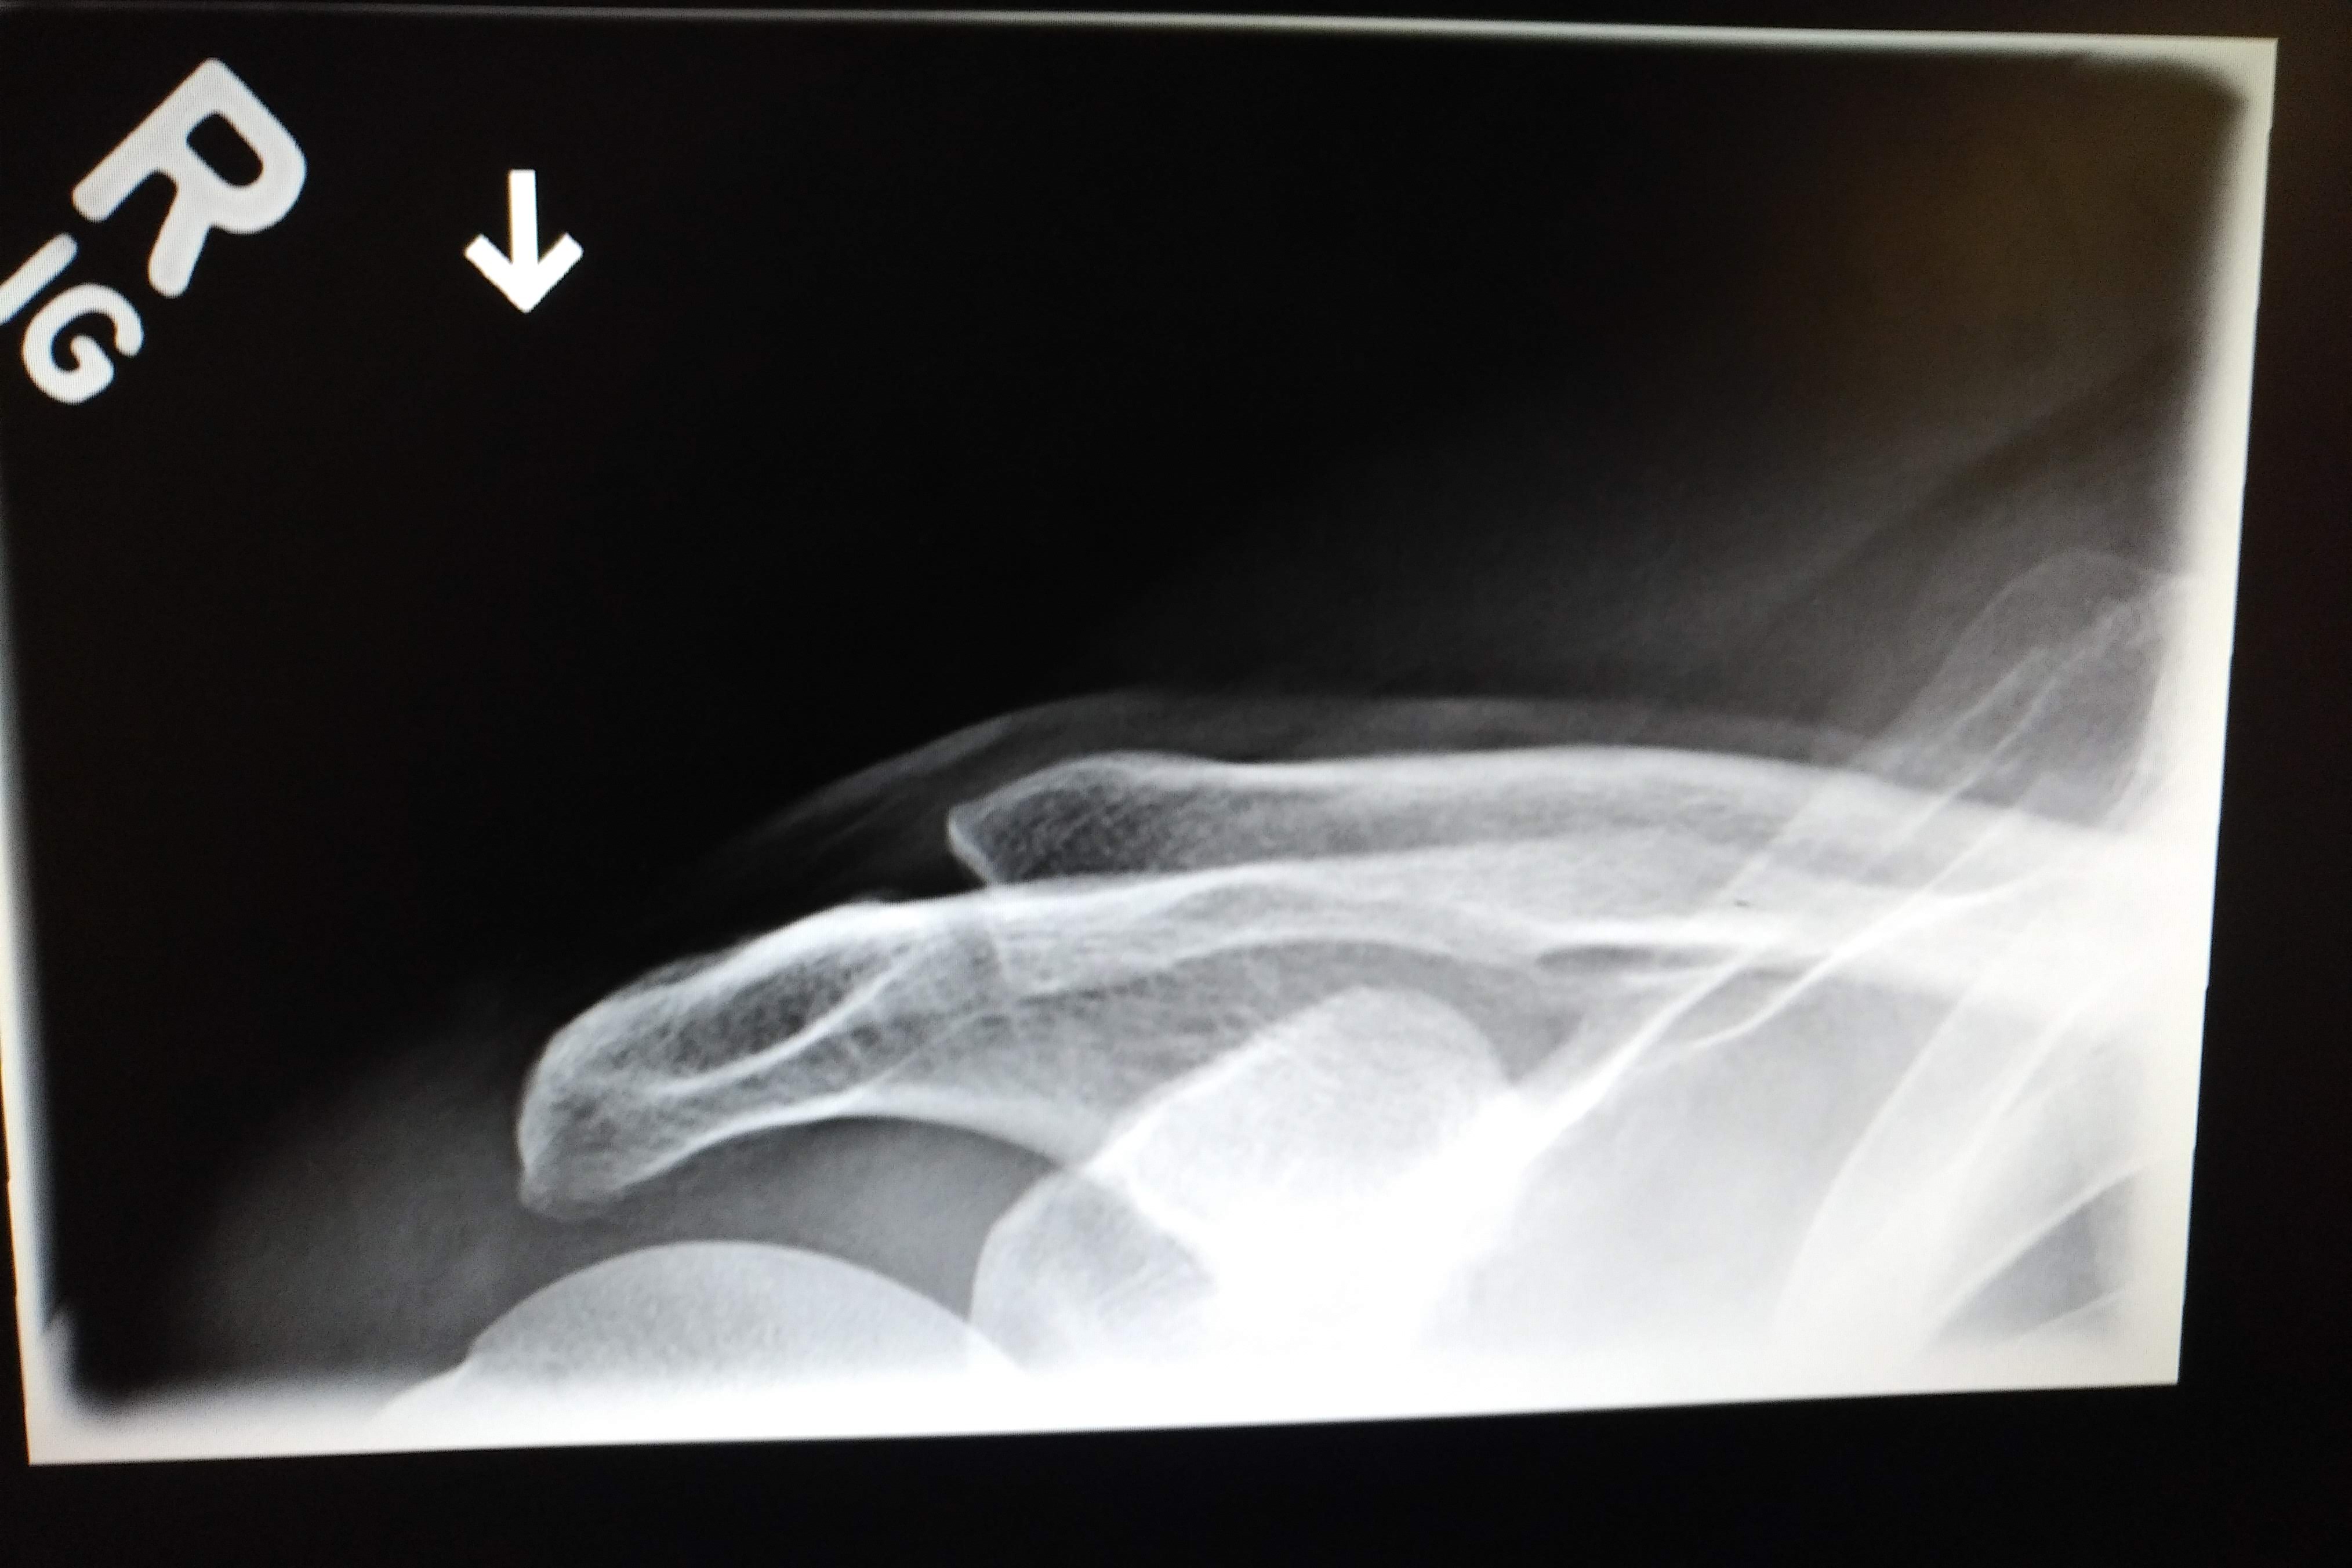

From shoulderinjury.blogspot.com

50kshoulder injury Learning Radiology clavicle, clavicular Clavicle Injury From Weight Lifting A breakdown of the bone. If you experience shoulder pain that gets worse when weight lifting, a popping/clicking sensation while moving your shoulder and tenderness to the touch, you may have a condition. The condition, sometimes called weightlifter's shoulder, is. The primary cause of distal clavicle osteolysis is repetitive microtrauma to the acromioclavicular (ac) joint during strength exercises, particularly those. Clavicle Injury From Weight Lifting.